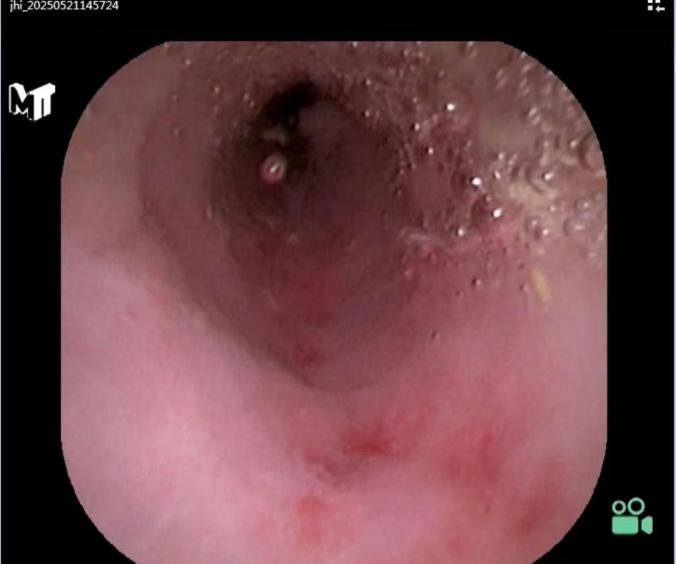

找到开口后,将一根更细的阑尾子镜通过结肠镜的活检孔道插入阑尾腔内。

阑尾子镜清晰显示阑尾内部结构、炎症程度以及是否存在罪魁祸首——粪石。

3. 引流:

对于脓液较多的严重病例,医生可能放置一根细小的塑料支架(引流管)在阑尾腔内,一端留在肠腔,持续引流几天,帮助炎症更快消退。